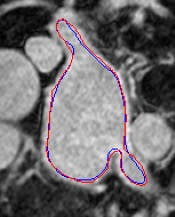

Automated segmentation in medical image analysis is a challenging task that requires a large amount of manually labeled data. However, most existing learning-based approaches usually suffer from limited manually annotated medical data, which poses a major practical problem for accurate and robust medical image segmentation. In addition, most existing semi-supervised approaches are usually not robust compared with the supervised counterparts, and also lack explicit modeling of geometric structure and semantic information, both of which limit the segmentation accuracy. In this work, we present SimCVD, a simple contrastive distillation framework that significantly advances state-of-the-art voxel-wise representation learning. We first describe an unsupervised training strategy, which takes two views of an input volume and predicts their signed distance maps of object boundaries in a contrastive objective, with only two independent dropout as mask. This simple approach works surprisingly well, performing on the same level as previous fully supervised methods with much less labeled data. We hypothesize that dropout can be viewed as a minimal form of data augmentation and makes the network robust to representation collapse. Then, we propose to perform structural distillation by distilling pair-wise similarities. We evaluate SimCVD on two popular datasets: the Left Atrial Segmentation Challenge (LA) and the NIH pancreas CT dataset. The results on the LA dataset demonstrate that, in two types of labeled ratios (i.e., 20% and 10%), SimCVD achieves an average Dice score of 90.85% and 89.03% respectively, a 0.91% and 2.22% improvement compared to previous best results. Our method can be trained in an end-to-end fashion, showing the promise of utilizing SimCVD as a general framework for downstream tasks, such as medical image synthesis and registration.